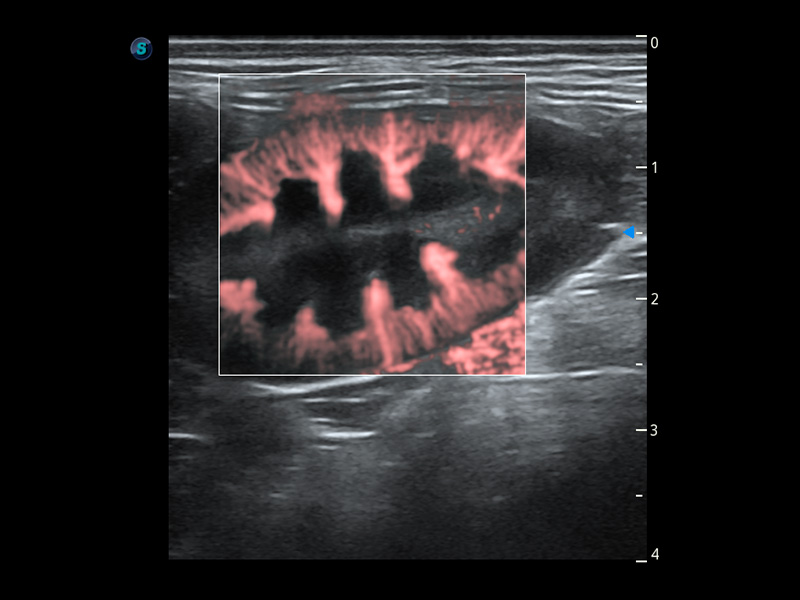

ProPet 60 作为一款高端台式动物超声设备,为动物医生的日常诊断提供了一系列贴合动物临床需求、解决临床实际问题的高级成像功能。凭借全系列高清探头,满足医生对腹部、心脏、生殖、浅表、肌骨等成像的所有需求,切实帮助您提升检查效率,提高诊断信心。

动物是人类最亲密的朋友和最值得信赖的伙伴。DB中国旗舰官方网站也一直致力于探索动物专用的超声影像解决方案。 全新推出的ProPet系列,是DB中国旗舰官方网站在动物超声影像智能化、专业化、精准化的一次跨越式革新。动物不能用言语来表述自己的不适,通过超声影像,ProPet系列搭建了动物医生与不同物种沟通的“桥梁”,为动物医生注入了“治愈之力”。